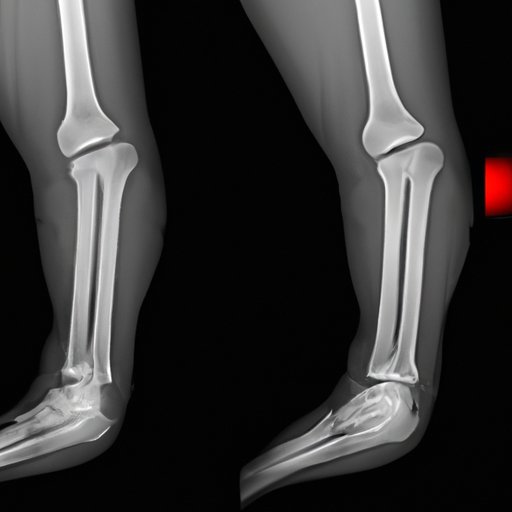

A compound fracture is a type of fracture that involves broken bone(s) breaking through the surrounding skin. This type of fracture is more severe than other types because it can cause severe damage to surrounding muscles and tissues. Compound fractures can occur in any bone, such as the ankle, thigh bone, forearm, or the wrist.

Fractures are classified based on the complexity of the break. Compound fractures belong to Grade III, the most severe type of fractures. A simple or closed fracture is when the bone breaks but does not pierce the skin. A comminuted fracture occurs when the bone is broken into several small pieces. A greenstick fracture is a partial break of the bone, commonly seen in children.

Compound fractures differ from simple fractures because the bone is not just broken, but a fragment of bone breaks through the skin. This type of fracture is extremely painful, and the open wound increases the risk of infection. If you suspect a compound fracture, seek medical attention immediately.

The symptoms and signs of a compound fracture can vary, depending on the location and severity of the injury. The most common symptom is intense pain that worsens with movement. You may also experience deformity of the affected area, swelling, and bruising. It is also possible to see the bone protruding through the skin.

Diagnosis of compound fractures involves a physical examination and diagnostic imaging tests, such as X-rays, CT scans, or an MRI. These tests can show the extent and severity of the fracture and identify any associated damage to the surrounding tissues.